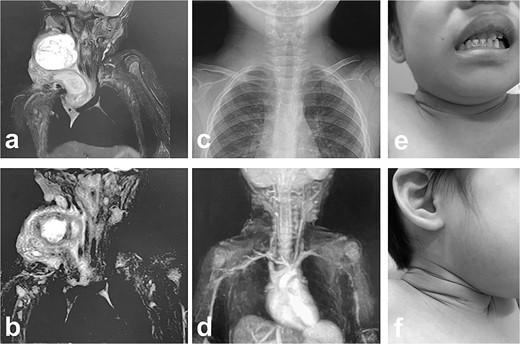

MRI findings after removal of the Denver shunt catheter. (a) MRI findings showed two different areas of intensity in the neck region and the mediastinal region where the Denver shunt was inserted. (b) MRI findings 2 months postoperatively showed that the mediastinal lesion was smaller with near-complete regression. (c) X-ray showed no tumor shadow and no compression of the trachea by the lymphangioma. (d) MRA showed disappearance of the lymphangioma. (e) and (f) Right cervical swelling did not become evident, even when crying (e: crying, f: smiling).